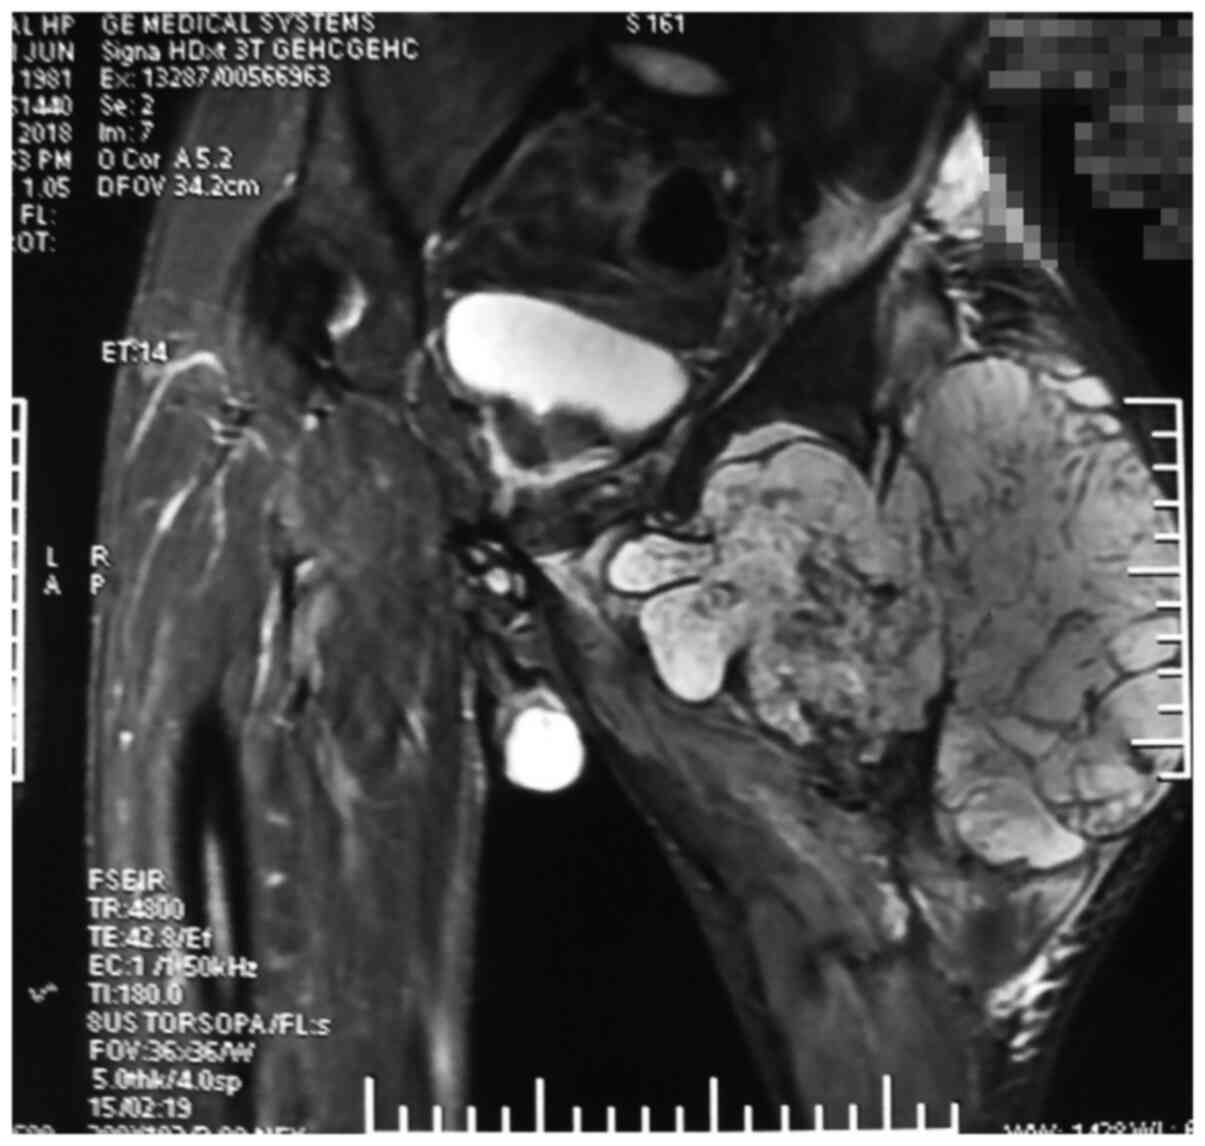

A 37-year-old man had initially developed an obvious mass on his left index, middle and index fingers at the age of 6 years; however, no special treatment was administered. After 30 years, the masses on the patient's hands had grown in size, acquiring a dendritic shape, and were accompanied by pain, leading to limited function and movement. Moreover, the left hand (Fig. 1A), left hip, left knee, left ankle and left foot (Fig. 1B) were swollen and this condition progressively became aggravated. The mass was hard and exhibited nodular changes. At a later stage, the mass in the left hip became rapidly enlarged and the patient was in obvious pain. He also visited relevant hospitals without receiving any special treatment. The patient came to the Second Affiliated Hospital of Shanxi Medical University for treatment in 2018 due to severe pain in the left hip joint. Since the onset of the disease, the patient did not have any symptoms of a frequent fever, fatigue, emaciation, dizziness, headaches, blurred vision or any other discomfort, In addition, the patient had no family history of any hereditary diseases, no history of exposure to any specific chemicals and radiation, and was a single farmer in occupation and did not use tobacco and consume alcohol. A physical examination upon admission revealed the following: The left lower extremity of the patient was significantly shorter than the right lower extremity, by ~10 cm. Dendritic-shaped masses were observed in the left hand, swelling and deformity were observed on the left hip, left knee and left foot, and the range of motion of the left hip and left knee was markedly restricted compared with that of the normal right hip and knee. An X-ray examination revealed multiple osteopathies of the left hand, left hip, left knee, left ankle and left foot (Fig. 2). A magnetic resonance imaging (MRI) examination of the hip revealed abnormal signals of bone and soft tissue in the proximal left femur (Fig. 3), and malignant lesions were considered. The clinical diagnosis of Ollier disease was thus made. The results of the patient's laboratory tests are presented in Table I. However, due to the clear diagnosis, the patient did not undergo radionuclide bone imaging and a computed tomography (CT) scan.

Figure 3

Bone destruction of the left hip joint and abnormal signal of the surrounding soft tissue can be seen. Post-operative pathological examination revealed that the lesion in the left hip joint developed into chondrosarcoma.

Radionuclide bone imaging is the most effective tool for the diagnosis of multiple lesions and malignant transformation (20). It can guide the clinical and prognostic analysis of Ollier disease. An X-ray is one of the most basic tools for the diagnosis of skeletal diseases. In Ollier disease, the lesions mostly appear in the shaft and metaphysis of short or long bone, and the lesions are mostly oval in shape. In short bone, the lesions can appear as scallop-like impressions due to the limited space, the cortical bone becomes thinner, and thus pathological fractures are common. In the long shaft, due to its large growth space, there is no characteristic scallop-like impression, and the bone cortex does not become thinner (21). It is more important to evaluate the lesion size and soft tissue invasion by a CT scan (16). The lesion is characterized by a round and lobulated density shadow, and the density is equal to or slightly lower than the muscle density shadow (22). A CT scan can also reveal different calcification patterns. It has been indicated that further attention should be paid to calcification patterns when predicting the development of chondrosarcoma (18). In the present study, the MRI revealed a round, quasi-round and striped density inhomogeneous signal in the medullary cavity, particularly soft tissue involvement. For example, in the present study, the MRI revealed the significant destruction of the left femoral cortex and extensive soft tissue involvement, combined with the rapid aggravation of short-term pain in the patient, considering the greater possibility of malignant chondrosarcoma; a biopsy also needs to be performed to determine the nature of the lesion before guiding clinical treatment.

On the whole, an X-ray can diagnose correctly typical cases. A CT scan can reveal calcification foci, which is of great significance in determining whether there a malignant alteration exists. An MRI examination can visualize the cartilage components in the lesions to further clarify the lesions and improve the accuracy of diagnosis.